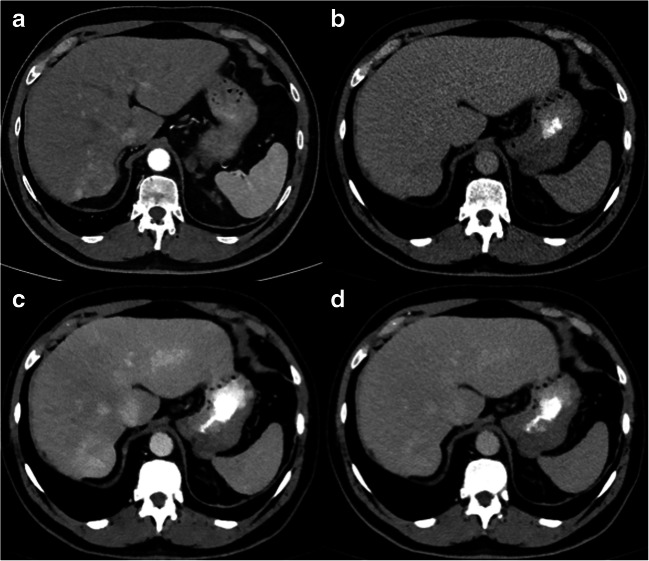

Image examples are shown in Figs. 4 and 5.

Fig. 4.

Axial CT images showing an arterially hyper-enhancing lesion in liver segment VII (a) with washout in delayed phase on CI (b), 40 keV (c) and 60 keV (d). However, washout and lesion-to-liver ratio were higher in 40-keV compared to 60-keV images and CIs, resulting in a better visibility